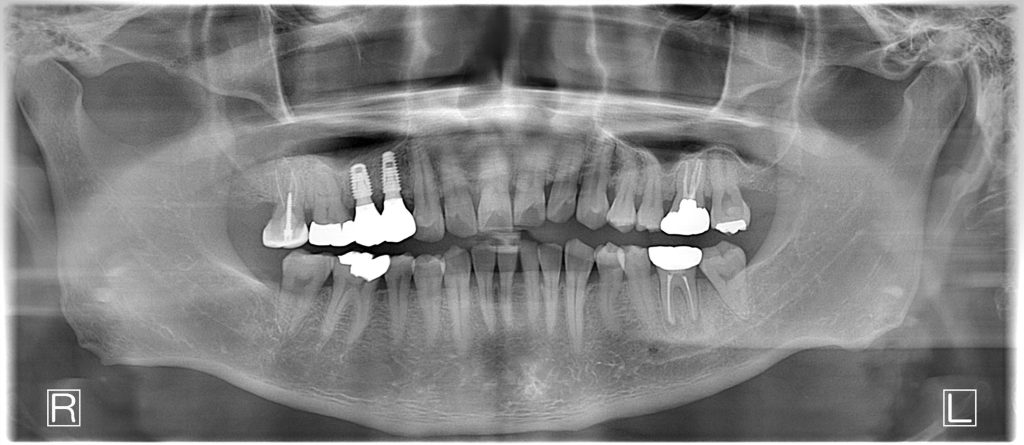

60代、男性。過去に治療途中で通わなくなり最近痛みが増してきたということで来院され、インプラント治療を行いました。

| 患者様の主訴 | 右上が痛い |

| 診断結果 | 右上4・5番重度う蝕、歯根破折 |

| 治療内容 | 抜歯即時インプラント |

| 治療期間 | 12週間 |

| 治療費用 | ¥94,600(税込) |